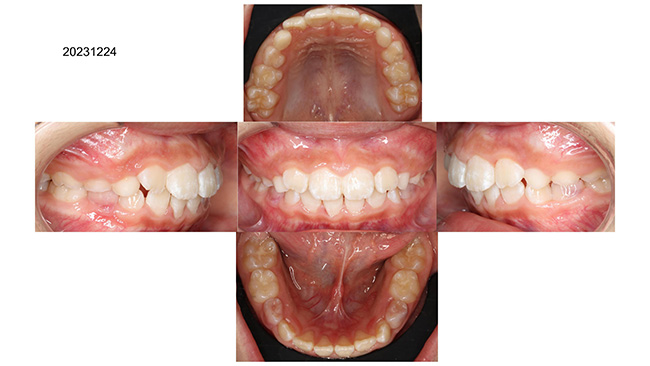

歯並びがガタガタの症例